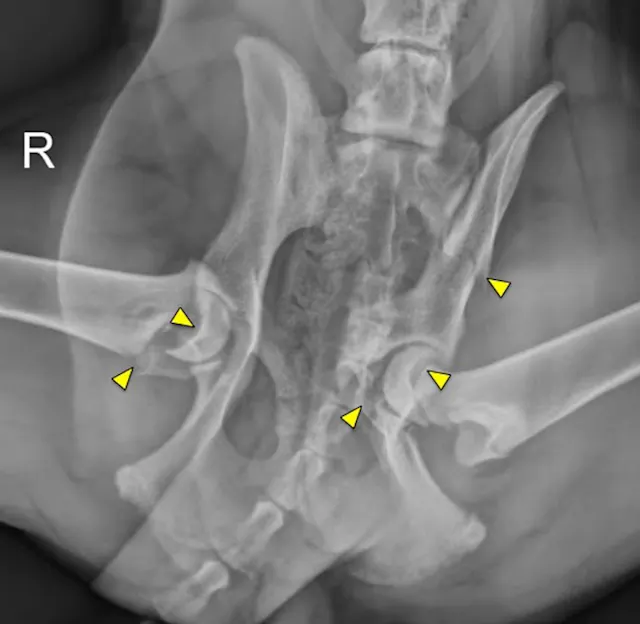

Physeal fractures are common in skeletally immature cats and dogs. Because they can often be difficult to detect on radiographs, a high index of suspicion of physeal injury is warranted in any traumatized puppy or kitten with pain or swelling around the joint. Early identification and timely reduction and stabilization of the fracture, along with careful monitoring, are important for a successful outcome.

Physeal fractures can occur in any juvenile animal, even with little trauma, because the physis is weaker than the adjacent bone and ligaments. Orthogonal radiographs of any painful joint should be performed. Oblique projections, radiographs of the limb in different positions, and radiographs of the contralateral limb for comparison can all aid in the diagnosis of a physeal fracture. Shown here are lateral stifle radiographs from an 8-month-old mixed breed dog that presented for acute onset of lameness in the left pelvic limb after he slipped earlier that evening; pain was localized to the left stifle. Notice the open physes of the proximal tibia and distal femur, which are normal for a dog of this age. There is physeal separation and cranial displacement of the proximal epiphysis in the left tibia, and a greenstick fracture of the left fibula (arrows).